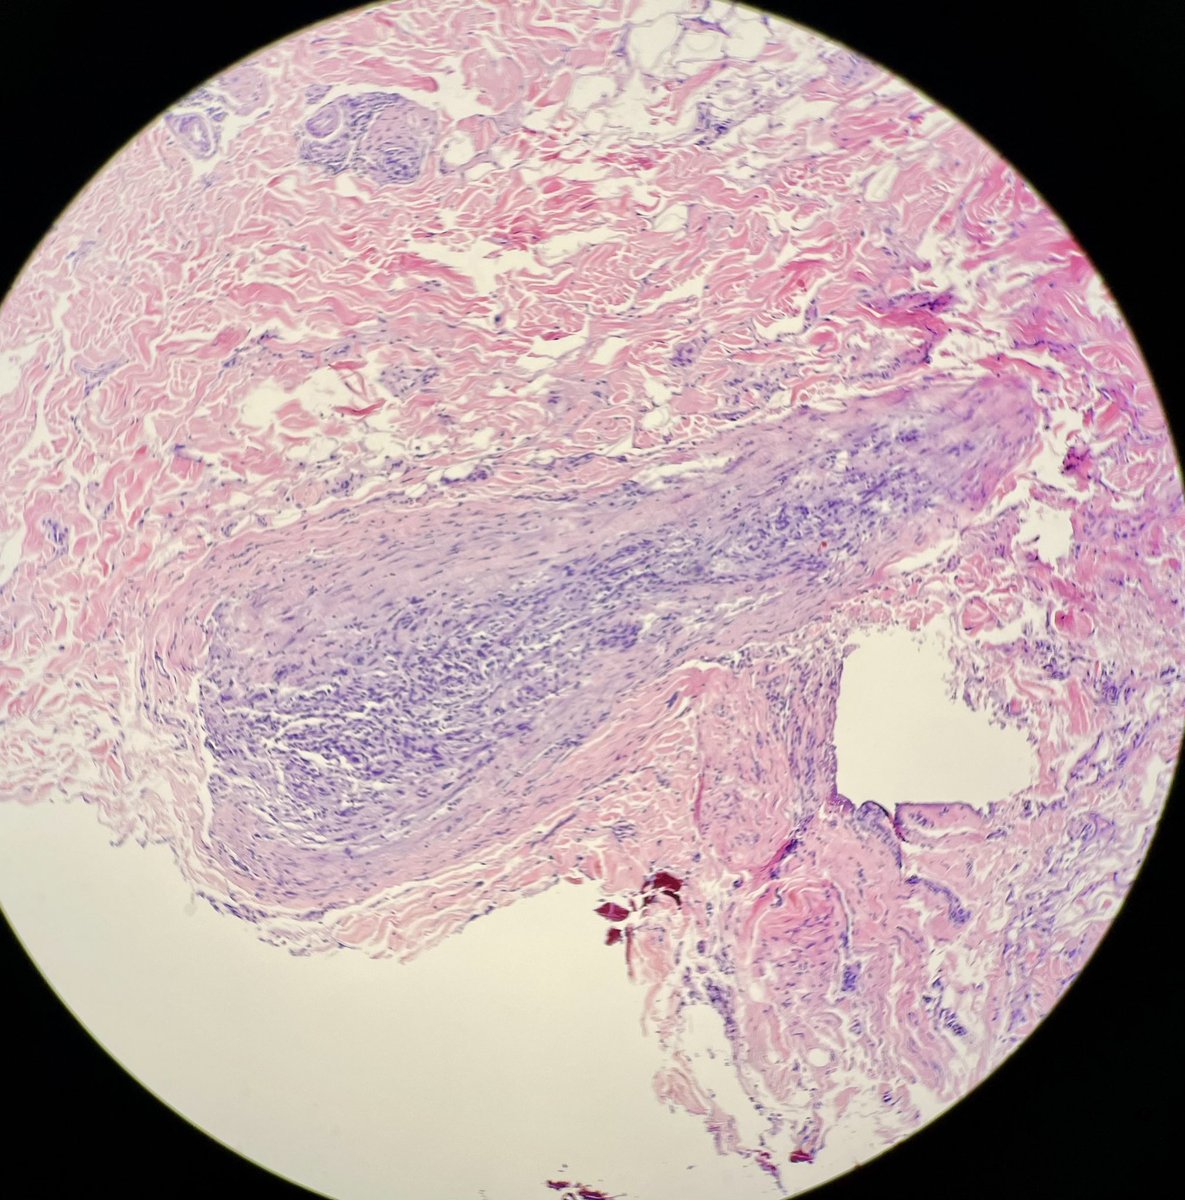

Silvija Gottesman MD Alejandro Gru (Ale) J Cutan Pathol Katy Veprauskas Maxwell Fung, MD Gregory A Hosler Henry YANG David Terrano Dermpath-L Dermpath_doc_trish Tristan Rutland MBBS FRCPA IFCAP Etan Marks, DO Maryam Aghighi, MD. DABP. Jerad Gardner, MD Cacey Peters, MD, FCAP, FASDP Pembe Oltulu, MD Walter Klein MD Andrea P Moy, MD Patrick Rush Jisun Cha MD FAAD Sara Shalin James A. Ramirez Joseph Susa, DO Rosalynn Nazarian MD 🅰🅼🆈🅷🅳🅴🅴🅺🅴🅽🅼🅳 Mariantonieta Tirado Vijay Shankar S Mike DeWall, D.O. Olaleke Folaranmi David Larson Luis Humberto Cruz C Kamran Mirza MD PhD - کامران مرزا Toño Navarro, M.D. 🔬🎗️ Nicole D. Riddle, MD, MSHI, FCAP (she/her) Haneen Salah Save the Date. Save the Date. Hot off the press. Next #dermpathJC to take place on 01/26/23 at 9pm EST, here on Twitter. Open access link at: jamanetwork.com/journals/jaman… #dermpath